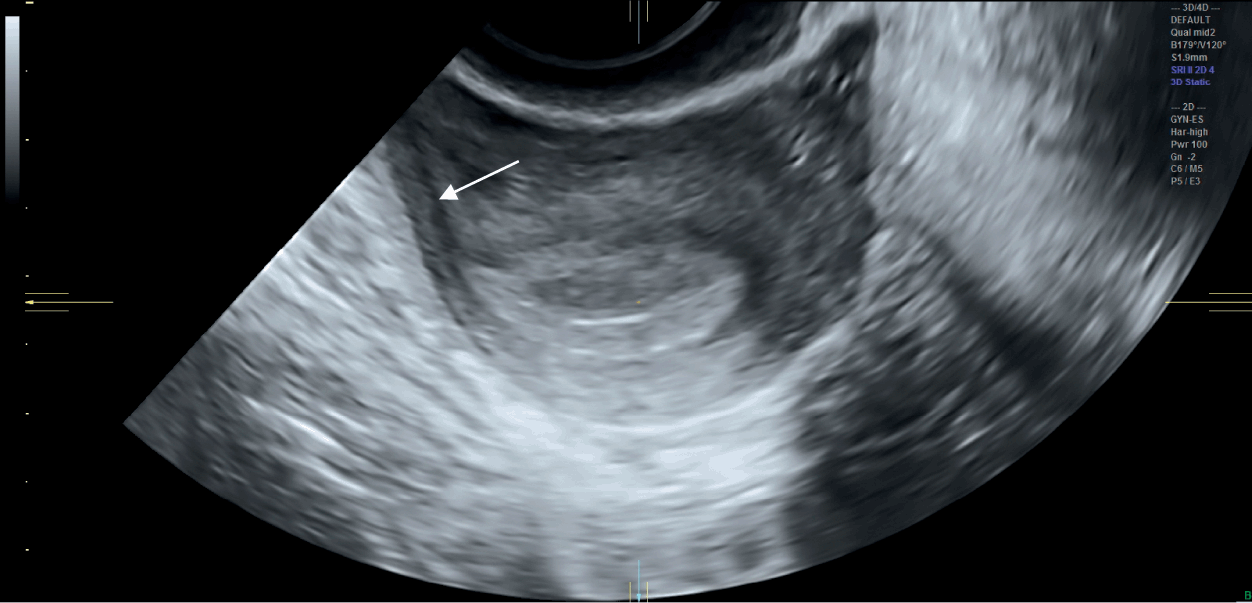

The accuracy of the EDD by ultrasound depends on several factors such as the current stage of pregnancy, the quality of the machine, and the position of the baby in the mother's womb . Therefore, it is safe to say that the accuracy of the ultrasound decreases as the pregnancy progresses . Hence ultrasounds cannot be 100 percent correct and reliable .

How Accurate Are Dating Scans ? Early dating scan accuracy is reliable to a remarkable degree . However, the system isn't fool-proof, and there are situations where accuracy can be compromised . Some of these situations include: The skill of the sonographer is an important part of the equation .

Due Date Accuracy . Naturally, one of the most common questions asked about ultrasound is : Just how accurate are due dates predicted by ultrasound? Evidence suggests that, in the first 20 weeks of pregnancy, the first ultrasound may be the most accurate tool for calculating a fetus's gestational ages .

But ultrasounds are not 100 % reliable for everything they measure . The accuracy of an ultrasound test can vary based on factors such as the stage of the pregnancy, the quality of the machine, the skill of the technician, and the position of the baby in your womb . 2 . Here's some info about the reliability of ultrasound for different . . .